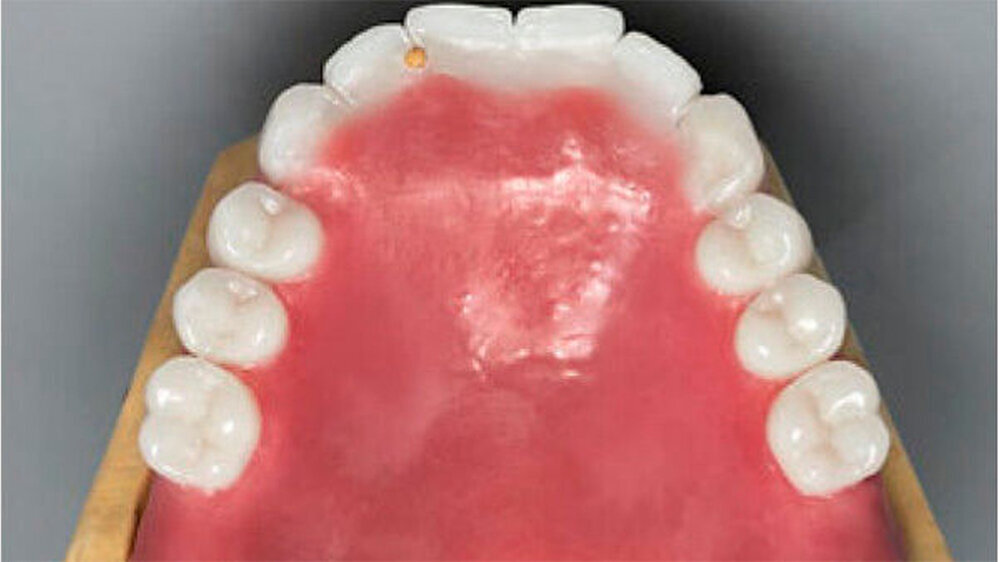

Um die Realisierbarkeit des Therapieziels zu überprüfen, erfolgte im Vorfeld eine diagnostische Aufstellung der Prothesenzähne im Ober- und im Unterkiefer, was eine adäquate Analyse des intra- und intermaxillären Platzangebots ermöglichte (Abb. 8 bis 10). Nun wurden die Pfeilerzähne für die Rekonstruktion mit Teleskopkronen präpariert (Abb. 11). Die individuellen Abformlöffel für die definitive Abformung entsprachen einem Duplikat der diagnostischen Aufstellungen des Ober- und Unterkiefers aus durchsichtigem Kunststoff. Dies ermöglichte gleichzeitig die Montage der Meistermodelle und die Übertragung der Gesamtaufstellung auf das Meistermodell.

Bei dieser bei Behandlungsbeginn 16-jährigen Patientin waren seit Geburt nur die beiden ersten Molaren im Oberkiefer ausgebildet. Die Folge waren schmale und niedrige Alveolarkämme mit einem flachen Gaumengewölbe (Abb. 16 und 17). Die röntgenologische Abbildung bestätigte das geringe vertikale Knochenangebot. Eine Formanomalie der Zahnwurzeln ließ auf taurodonte Molaren schließen. Beide Molaren wiesen ausgedehnte kariöse Läsionen auf (Abb. 18).